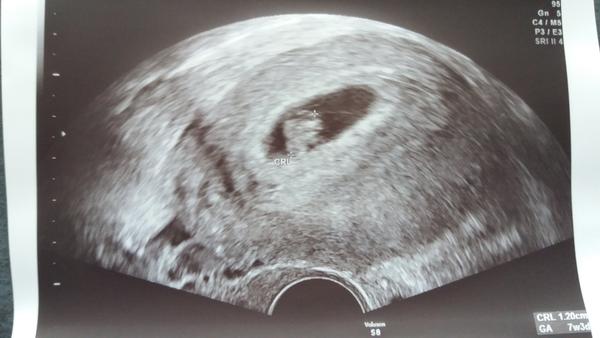

@lenkatorka Krásný ultrazvuk. Tak ať se miminku i tobě daří 🙂

@renulkka moc děkuji. Teprve pátý tyden